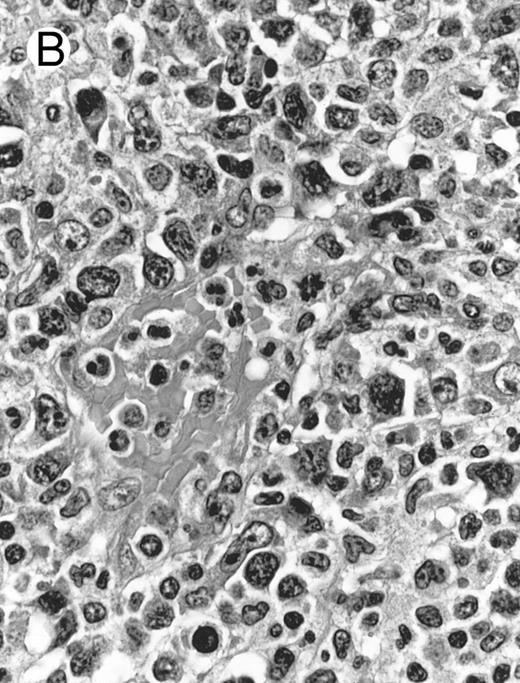

Blastoid NK cell lymphoma (case no. 40). (A) Biopsy shows a diffuse lymphomatous infiltrate with a prominent single-file pattern. (B) The neoplastic cells are medium-sized and possess fine chromatin. Mitotic figures are seen. There is remarkable resemblance to myeloid leukemic infiltration.

Blastoid NK cell lymphoma (n = 2).One patient presented with systemic disease, whereas 1 had localized disease at presentation. Histologically, the infiltrate was diffuse, with a prominent single-file pattern reminiscent of leukemia (Fig 8A). The neoplastic cells were medium-sized and had irregularly folded delicate nuclear membranes, fine chromatin, and tiny nucleoli (Fig 8B). Mitotic figures were easily identified.

In case no. 40, the immunophenotype was CD2− CD3/Leu4− CD4− CD5− CD7+ CD8− CD13− CD33+ CD56+, as analyzed on fresh tissue, and CD3ε+ (weak) CD43+ CD56+ CD68− TdT− and myeloperoxidase-negative on paraffin sections. In case no. 41, the immunophenotype as assessed on paraffin section was CD3ε+ CD43+ CD56+ TdT− and myeloperoxidase-negative. Both cases were EBERs-negative.